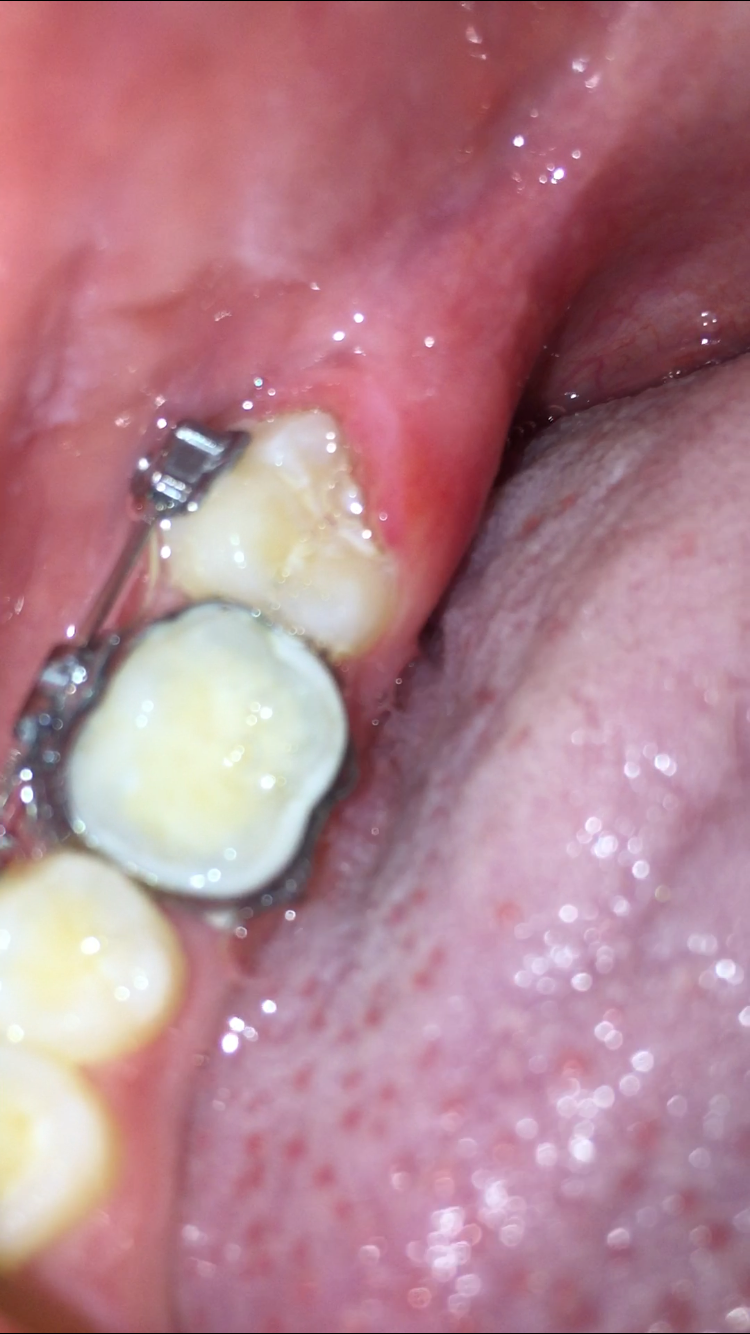

Zahnfleisch Wächst über Zahn. Warum wächst das Zahnfleisch über den Zahn? YesSmile Außerdem sind die Zahnhälse oft schmerzempfindlich und es kann beim Essen von kalten oder warmen Speisen ziehender Schmerz auftreten Zahnfleischwucherung: Welche Ursachen gibt es und was hilft? Die Zahnfleischwucherung (Gingivahyperplasie oder Gingivahypertrophie) äußert sich in einem Volumenzuwachs des Zahnfleischs

Diese Erkrankung kann verschiedene Ursachen haben, wie beispielsweise hormonelle Veränderungen, Medikamente oder Zahnfleischentzündungen. Diese Erkrankung kann verschiedene Ursachen haben, wie beispielsweise hormonelle Veränderungen, Medikamente oder Zahnfleischentzündungen. Erfahren Sie, warum das Zahnfleisch über den Zahn wächst, welche Ursachen es gibt und welche Behandlungsoptionen zur Verfügung stehen.

Zahnfleischbehandlung Gemeinschaftspraxis. Erfahren Sie, warum das Zahnfleisch über den Zahn wächst, welche Ursachen es gibt und welche Behandlungsoptionen zur Verfügung stehen. Es wächst über den Zahn, Rötungen des Zahnfleischs treten auf sowie Blutungen beim Zähneputzen oder bei der Verwendung von Zahnseide